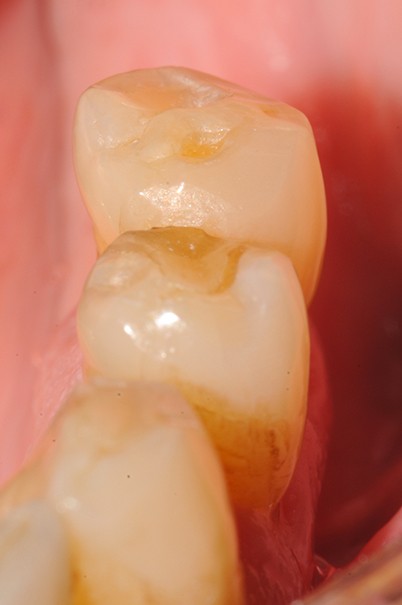

Aspect clinique et radiographique des lésions d’abrasion

Cliniquement, les lésions d’abrasion sont caractérisées par des facettes lisses, une absence de convexité et des bords à angles vifs. La flexibilité du ligament alvéolo-dentaire va entrainer un frottement au niveau des points de contact, qui peuvent se transformer en surfaces de contact (fig. 2c-d, 3 et 4b-c).